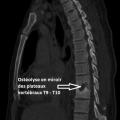

Ostéolyse vertébrale évocatrice de spondylodiscite évolutive

OSTEOLYSE

DISCITE